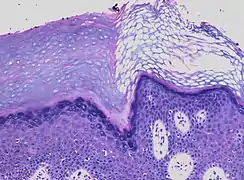

In contrast, hyperkeratosis (pictured) may also show a heterogeneous stratum corneum, but a preserved granular layer is seen.

In contrast, hyperkeratosis (pictured) may also show a heterogeneous stratum corneum, but a preserved granular layer is seen.